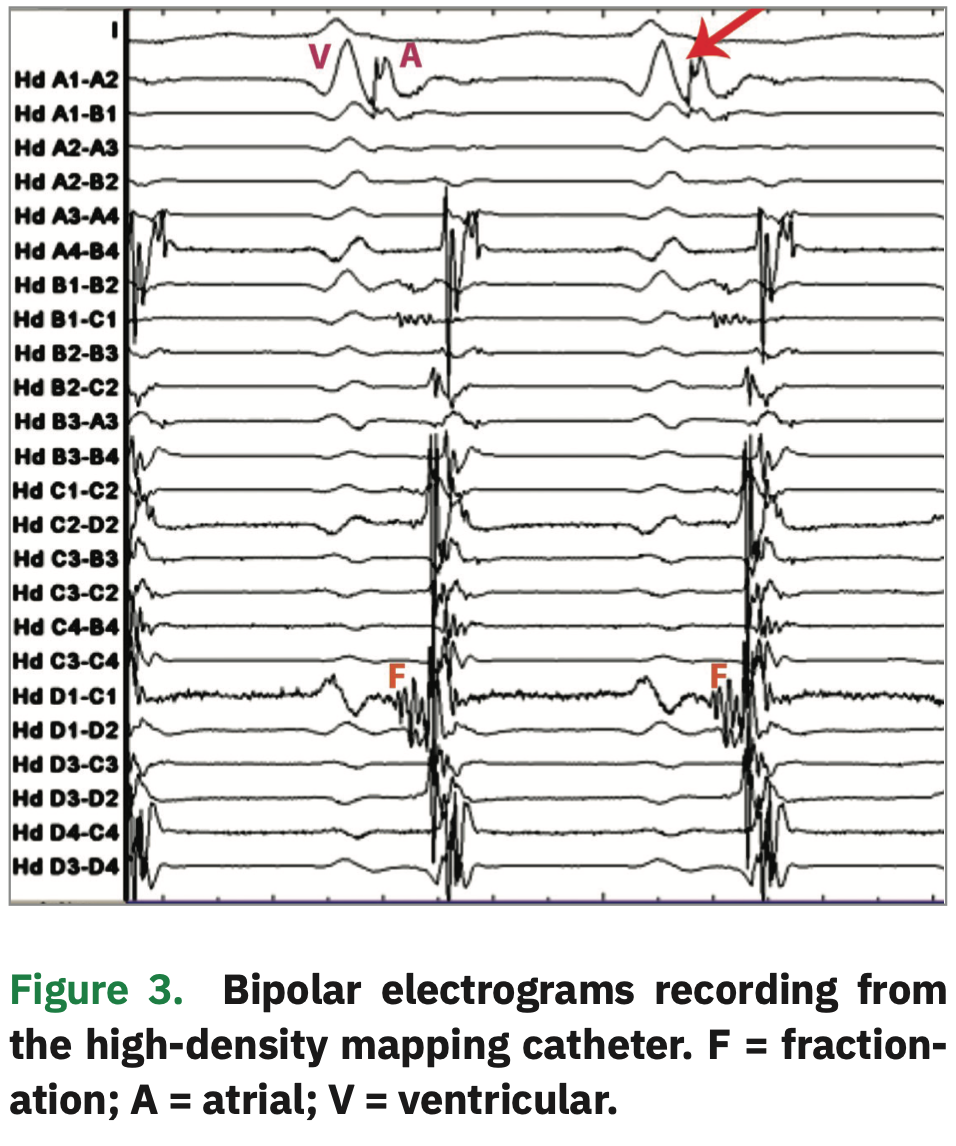

Mapping of a Left Lateral Accessory Pathway with a HighDensity What Is A Mapping Catheter Cardiac mapping is the process of recording the electrical activity of the heart in order to create a dynamic electroanatomic picture of that activity. It can be used to direct endocardial ablation treatment for stable. Acqmap (acutus medical) is an imaging and mapping system. Electroanatomic mapping (eam) is one such advancement, allowing operators to record intracardiac electrical activation in relation. What Is A Mapping Catheter.